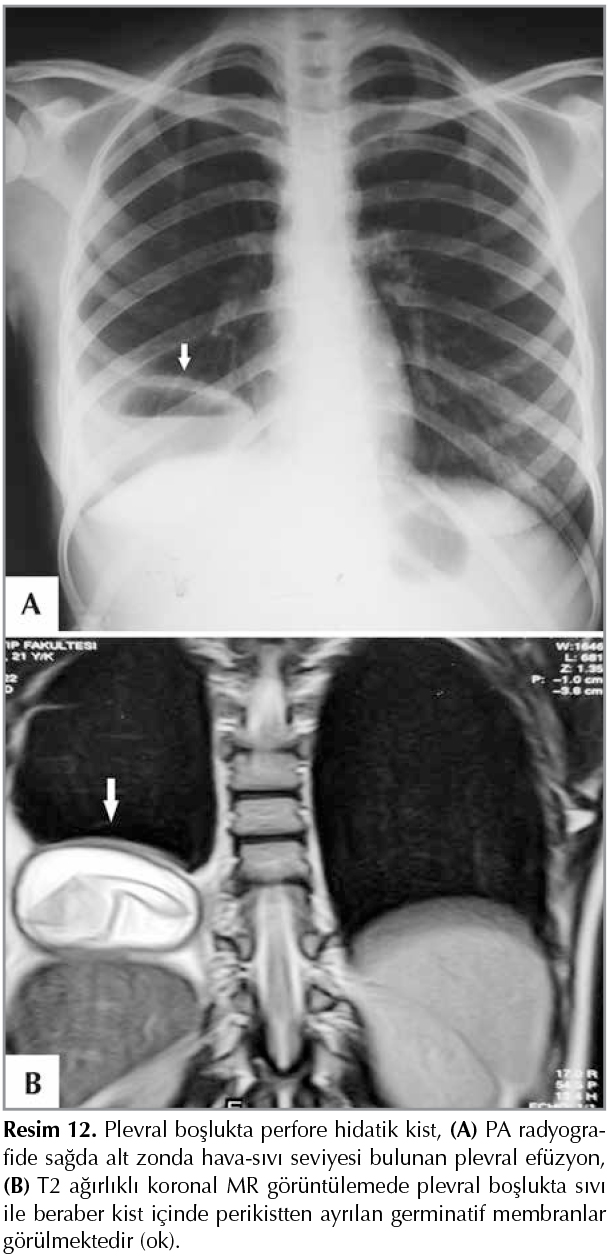

Asbest Temasına Bağlı Plevra Hastalıkları

Asbest lifsi yapıda (uzunluğu 10 mikrometre) mineral olup ısı, su ve strese y?ksek dayanıklı bir maddedir. Bu ?zelliği nedeniyle değişik iş kollarında ara madde olarak kullanılmaktadır. İ? Anadolu, G?neydoğu Anadolu ve Doğu Anadolu b?lgelerinde kırsal kesimde asbest i?eren ak toprak veya ?orak olarak adlandırılan toprak ısı ve su yalıtım amacıyla evlerin ?atısında ?rt? ve duvarlarında badana olarak kullanılmaktadır. Ak toprak i?erdiği asbest lifleri nedeniyle kırsal alanlarda yaşayanlarda doğumdan itibaren asbest temasının oluşmasına neden olmaktadır. Asbest temasına bağlı meydana gelen hastalıklar; plevral plaklar, benign plevral ef?zyon, yaygın plevral kalınlaşma, yuvarlak atelektazi ve malign plevral mezotelyomadır (20,21).

Asbest liflerine uzun s?re ve y?ksek konsantrasyonda maruz kalma sonucunda parankimde fibrozise (asbestozis), d?ş?k konsantrasyonda ve aralıklı maruz kalmada ise plevra hastalıkları daha sık g?r?lmektedir. Asbest lifleri solunum yoluyla inhale edildikten sonra peribronkovask?ler interstisyumdaki boşluklardan subplevral alana ilerlemekte ve buradan da mezotel h?creleri yoluyla plevral boşluğa ulaşmaktadır (20,22,23).

Plevra Plakları

Asbest temasının en yaygın bulgusudur. Bu bulgu asbest temasından 20 yıl veya daha fazla s?re ge?meden PA radyografide g?r?lmeyebilir. Plevral plaklar ?ncelikle pariyetal plevranın veya g?ğ?s duvarının posterolateralinde 7 ve 10. kostalar arasında, lateral g?ğ?s duvarında 6 ve 9. kostalar arasında, diyafragma kubbesinde plato şeklinde, d?zg?n veya nod?ler plevral kalınlaşmalar şeklinde g?r?lmektedir. Genellikle plaklar pariyetal plevrada g?r?lmesine rağmen visseral plevrada da g?r?lebilir. Plevral plakların g?sterilmesinde oblik radyografiler yararlıdır (20-23). Plaklar lateral pozisyonda yan g?ğ?s duvarının i? y?zeyine paralel, kalınlığı 1-10 mm olan yumuşak dansitede sınırları belirli dens bant şeklinde g?r?lebilir. Frontal pozisyonda plaklar sınırları belirsiz pe?e veya ?rt? şeklinde g?r?l?r. Kaynaklarda plevral plakların d?ş?k oranda postmortem olarak saptandığı belirtilmektedir (23,24).